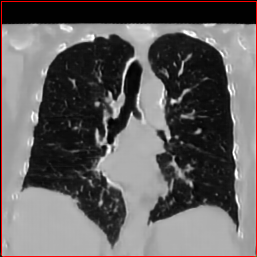

Figure 3 shows the generalizability of MAISI-v2 ControlNet for different body regions and voxel sizes. Figure 4 shows qualitative results for MAISI-v2 ControlNet on 5 types of tumors.

Lung Tumor

0.75×0.75×0.60.75\times 0.75\times 0.6

mm

512×512×512512\times 512\times 512

Figure 4: MAISI-v2 segmentation-guided results for five types of tumors. We show results for different voxel spacing and volume size to demonstrate the flexibility of MAISI-v2. Different Hounsfield Unit window is used to better show the contrast between tumor and normal tissues.